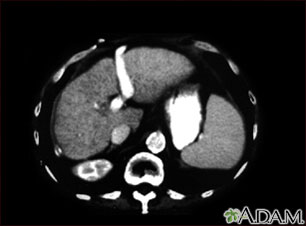

Liver cirrhosis - CT scan

A CT scan of the upper abdomen showing cirrhosis of the liver.